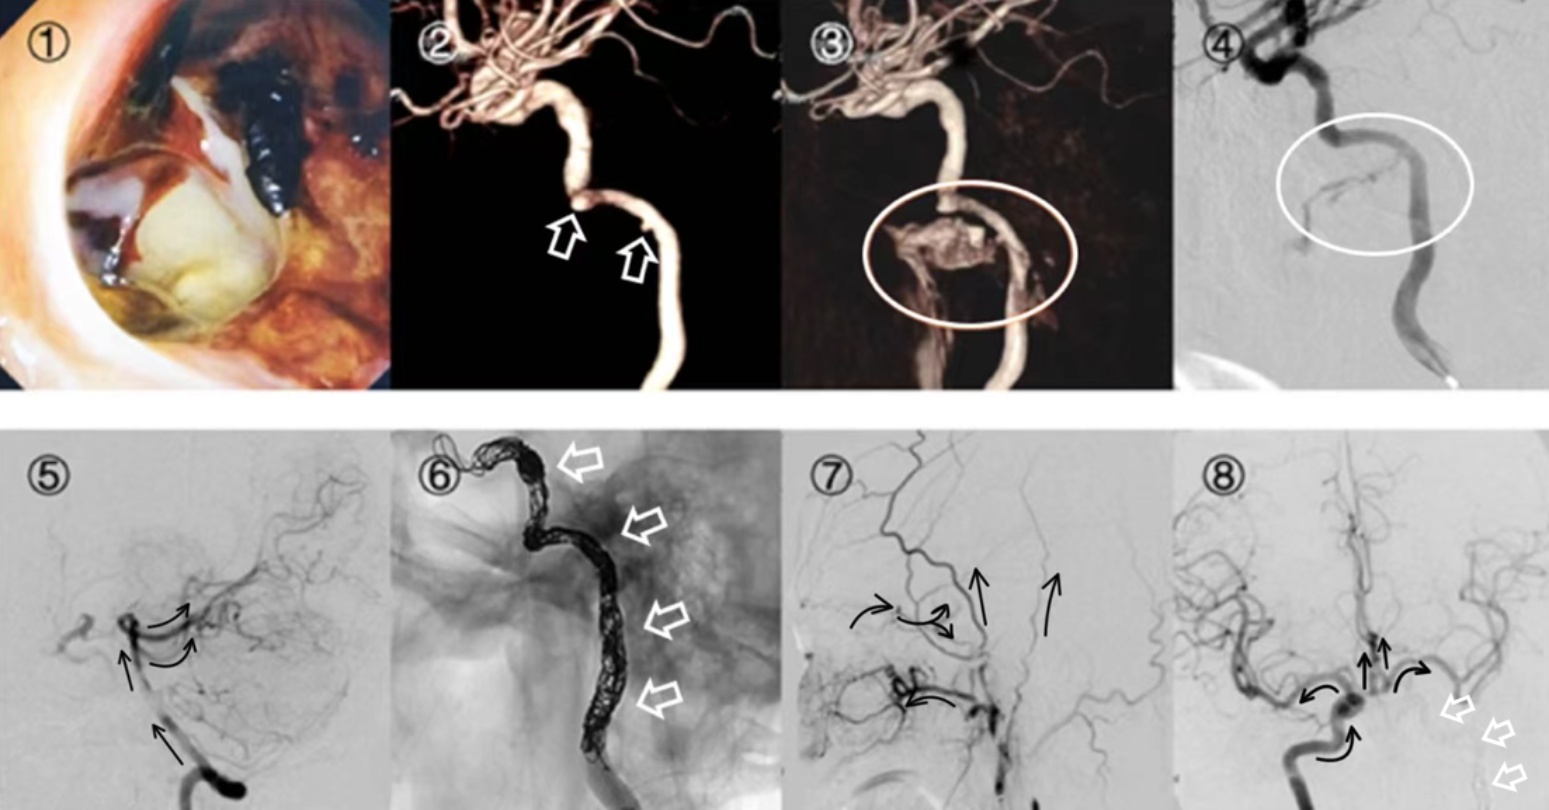

患者入院后完善相关检查,排除创伤、炎症、凝血功能障碍等常见鼻出血的原因,暂时考虑为鼻咽放化疗导致鼻出血。拟当日急诊介入手术室局麻下行“椎动脉造影 + 脑血管造影术”,同时备肿瘤供血动脉栓塞术。术中造影提示:左侧颈内动脉岩骨段有两个局限性小凸起,其一位于水平段,大小约2 × 2 mm,另一位于水平段与垂直段交界处,大小约2 × 2 mm,未见活动性出血,未见造影剂渗出,术中未行进一步处理(如图1②)。入院第二天患者再发鼻出血,部分血液由口咽部吐出,无法自行止血,患者自觉每次左侧鼻咽部有搏动、灼烧感,予以冰敷、苏灵及膨胀海绵填塞鼻腔止血后出血缓解。急查生化、血常规、凝血功能及鼻咽部MRI,完善头颅MRA后送介入手术室局麻下行“脑血管造影术”。术中造影(如图1③、图1④)提示:左侧颈内动脉C2~C4段假性动脉瘤并鼻出血及外耳道出血。造影结束后撤出造影用导管,用引导管插入左颈内动脉,通过导管在左颈内动脉C2~C4段的近心端放置一个球囊,充盈球囊完全阻断左颈内动脉的血流(如图1⑤),可见球囊以远不显影。再依次行右侧颈内动脉及椎动脉造影,见前交通及后交通向左侧颈内动脉代偿良好。球囊充盈维持30 min,观察患者见其生命体征平稳,无明显神经学症状及体征,提示颈内动脉球囊闭塞试验(balloon occlusion test, BOT)阴性,可以耐受颈内动脉闭塞,故选择永久性颈内动脉栓塞术,行经导管颅内动脉瘤裸弹簧圈栓塞术(如图1⑥),术后造影(如图1⑦、图1⑧)可见颈内动脉栓塞完全,颈外动脉造影见眼动脉段通过眼动脉代偿良好,右侧颈内动脉造影见前交通向左侧代偿良好。术中进一步诊断:左侧颈内动脉C2~C4段假性动脉瘤。术后予监测生命体征、预防感染、补液等对症支持治疗,请肿瘤科、影像科、介入科会诊,了解患者情况及评估潜在风险,患者无再发鼻出血,病情稳定。

Figure 1. ① Endoscopy of the left nasopharynx; ② First DSA with 3D reconstruction showing a localized protrusion of the left internal carotid artery; ③ ④ Second DSA with 3D reconstruction showing significant contrast leakage; ⑤ Assessment of permanent carotid embolization feasibility with adequate collateral supply observed after intraoperative compression of the left common carotid artery; ⑥ Post-embolization of the internal carotid artery; ⑦ ⑧ Postoperative DSA showing good collateral supply

1. ① 鼻咽镜下鼻咽左侧;② 第一次行DSA后三维重建,见左侧颈内动脉局限性凸起;③ ④ 第二次行DSA所见及三维重建,术中见造影剂外渗明显;⑤ 评估永久性颈内动脉栓塞术的可行性,术中压闭左侧颈总动脉后见交通支血供良好;⑥ 永久性颈内动脉栓塞术后;⑦ ⑧ 术后行DSA查看代偿血供良好